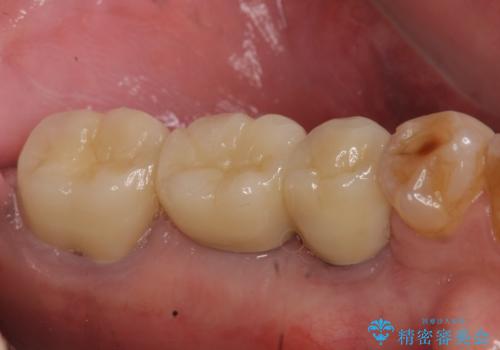

欠損部位である左下5、6番目にインプラントを埋入し、オールセラミッククラウンによる補綴を行いました。

左下7番目は再根管治療を行い、オールセラミッククラウンによる補綴を行いました。

オールセラミッククラウンについて

今回用いたオールセラミッククラウンはジルコニアフレームという白い素材の上にセラミックを盛っているため、審美性が非常に高いのが特徴です。

また、ジルコニアは人工ダイヤモンドの材料にも使われているほど高い強度を持っており、そのためオールセラミッククラウンは審美性だけでなく、奥歯やブリッジの補綴も可能とするクラウンです。